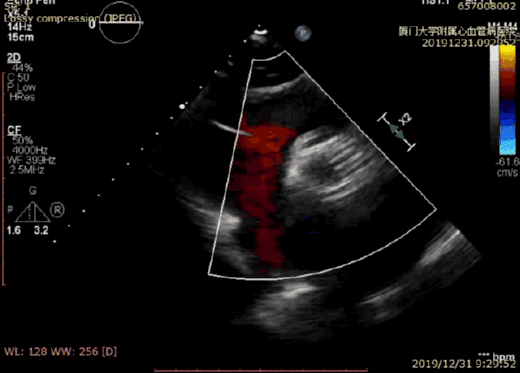

术后超声显示无瓣周漏

不到2小时的手术时间,王焱院长带领的心脏团队成功完成了TAVI手术。陈奶奶主动脉瓣重度狭窄的情况得以解除,主动脉根部-左心室压差由术前的74mmHg降到了4mmHg,患者左心功能恢复正常,术后即撤除了IABP。